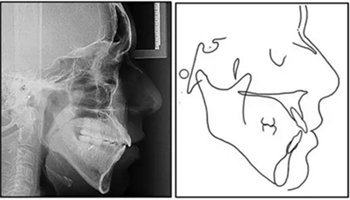

影像學(xué):全景片示:牙根平行度可。頭顱側(cè)位片及疊加圖示:下頜骨發(fā)生逆時(shí)針旋轉(zhuǎn),面部輪廓改善;上切牙轉(zhuǎn)矩正常,下切牙輕微舌傾;唇突度減小,鼻唇角增大。